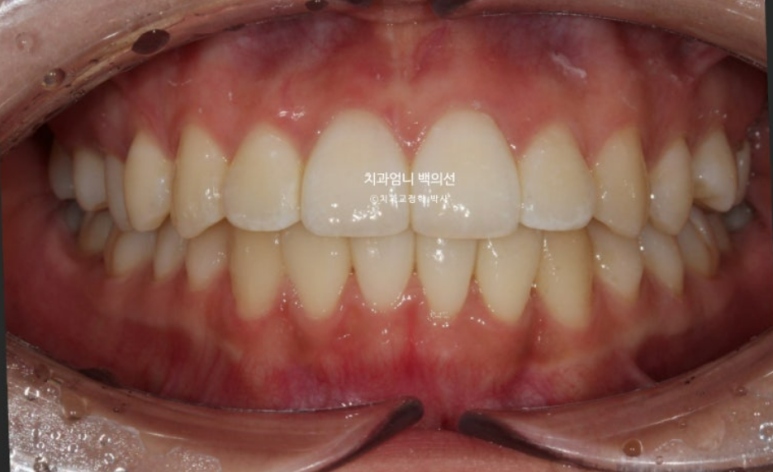

24년 9월 드디어 치료가 마무리되었습니다.

24.09

아무래도 파란 화살표 작은어금니 덧니가 옥의티죠?

아쉽지만, 환자분이 투자한 비용과 시간, 노력 대비 앞니 부분교정 급속교정 만으로도 좋은 효과를 봤으니 눈을 질끈 감겠습니다.

유지장치까지 붙은 모습입니다. 총 치료기간은 9개월입니다.